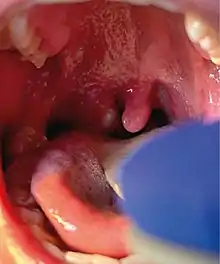

Right tonsillar enlargement with an overlying pustular lesion during the 2022 outbreak.

It is possible for a person to be infected with monkeypox virus without showing any symptoms.[33] Mpox symptoms tend to begin 5 to 21 days after infection,[34] with early symptoms including headache, muscle pains, fever and fatigue, initially resembling influenza.[3][35][36] Within a few days of the fever, lesions characteristically appear on the face before appearing on the trunk then elsewhere such as palms of the hands and soles of the feet.[37][38] The disease can resemble chickenpox, measles and smallpox but is distinguished by the presence of swollen glands[3][35] which may appear behind the ear, below the jaw, in the neck or in the groin, before the onset of the rash.[8] Many cases in the 2022 mpox outbreak presented with genital and peri-anal lesions, fever, swollen lymph nodes, and pain when swallowing,[1] with some patients manifesting only single sores from the disease.[39]